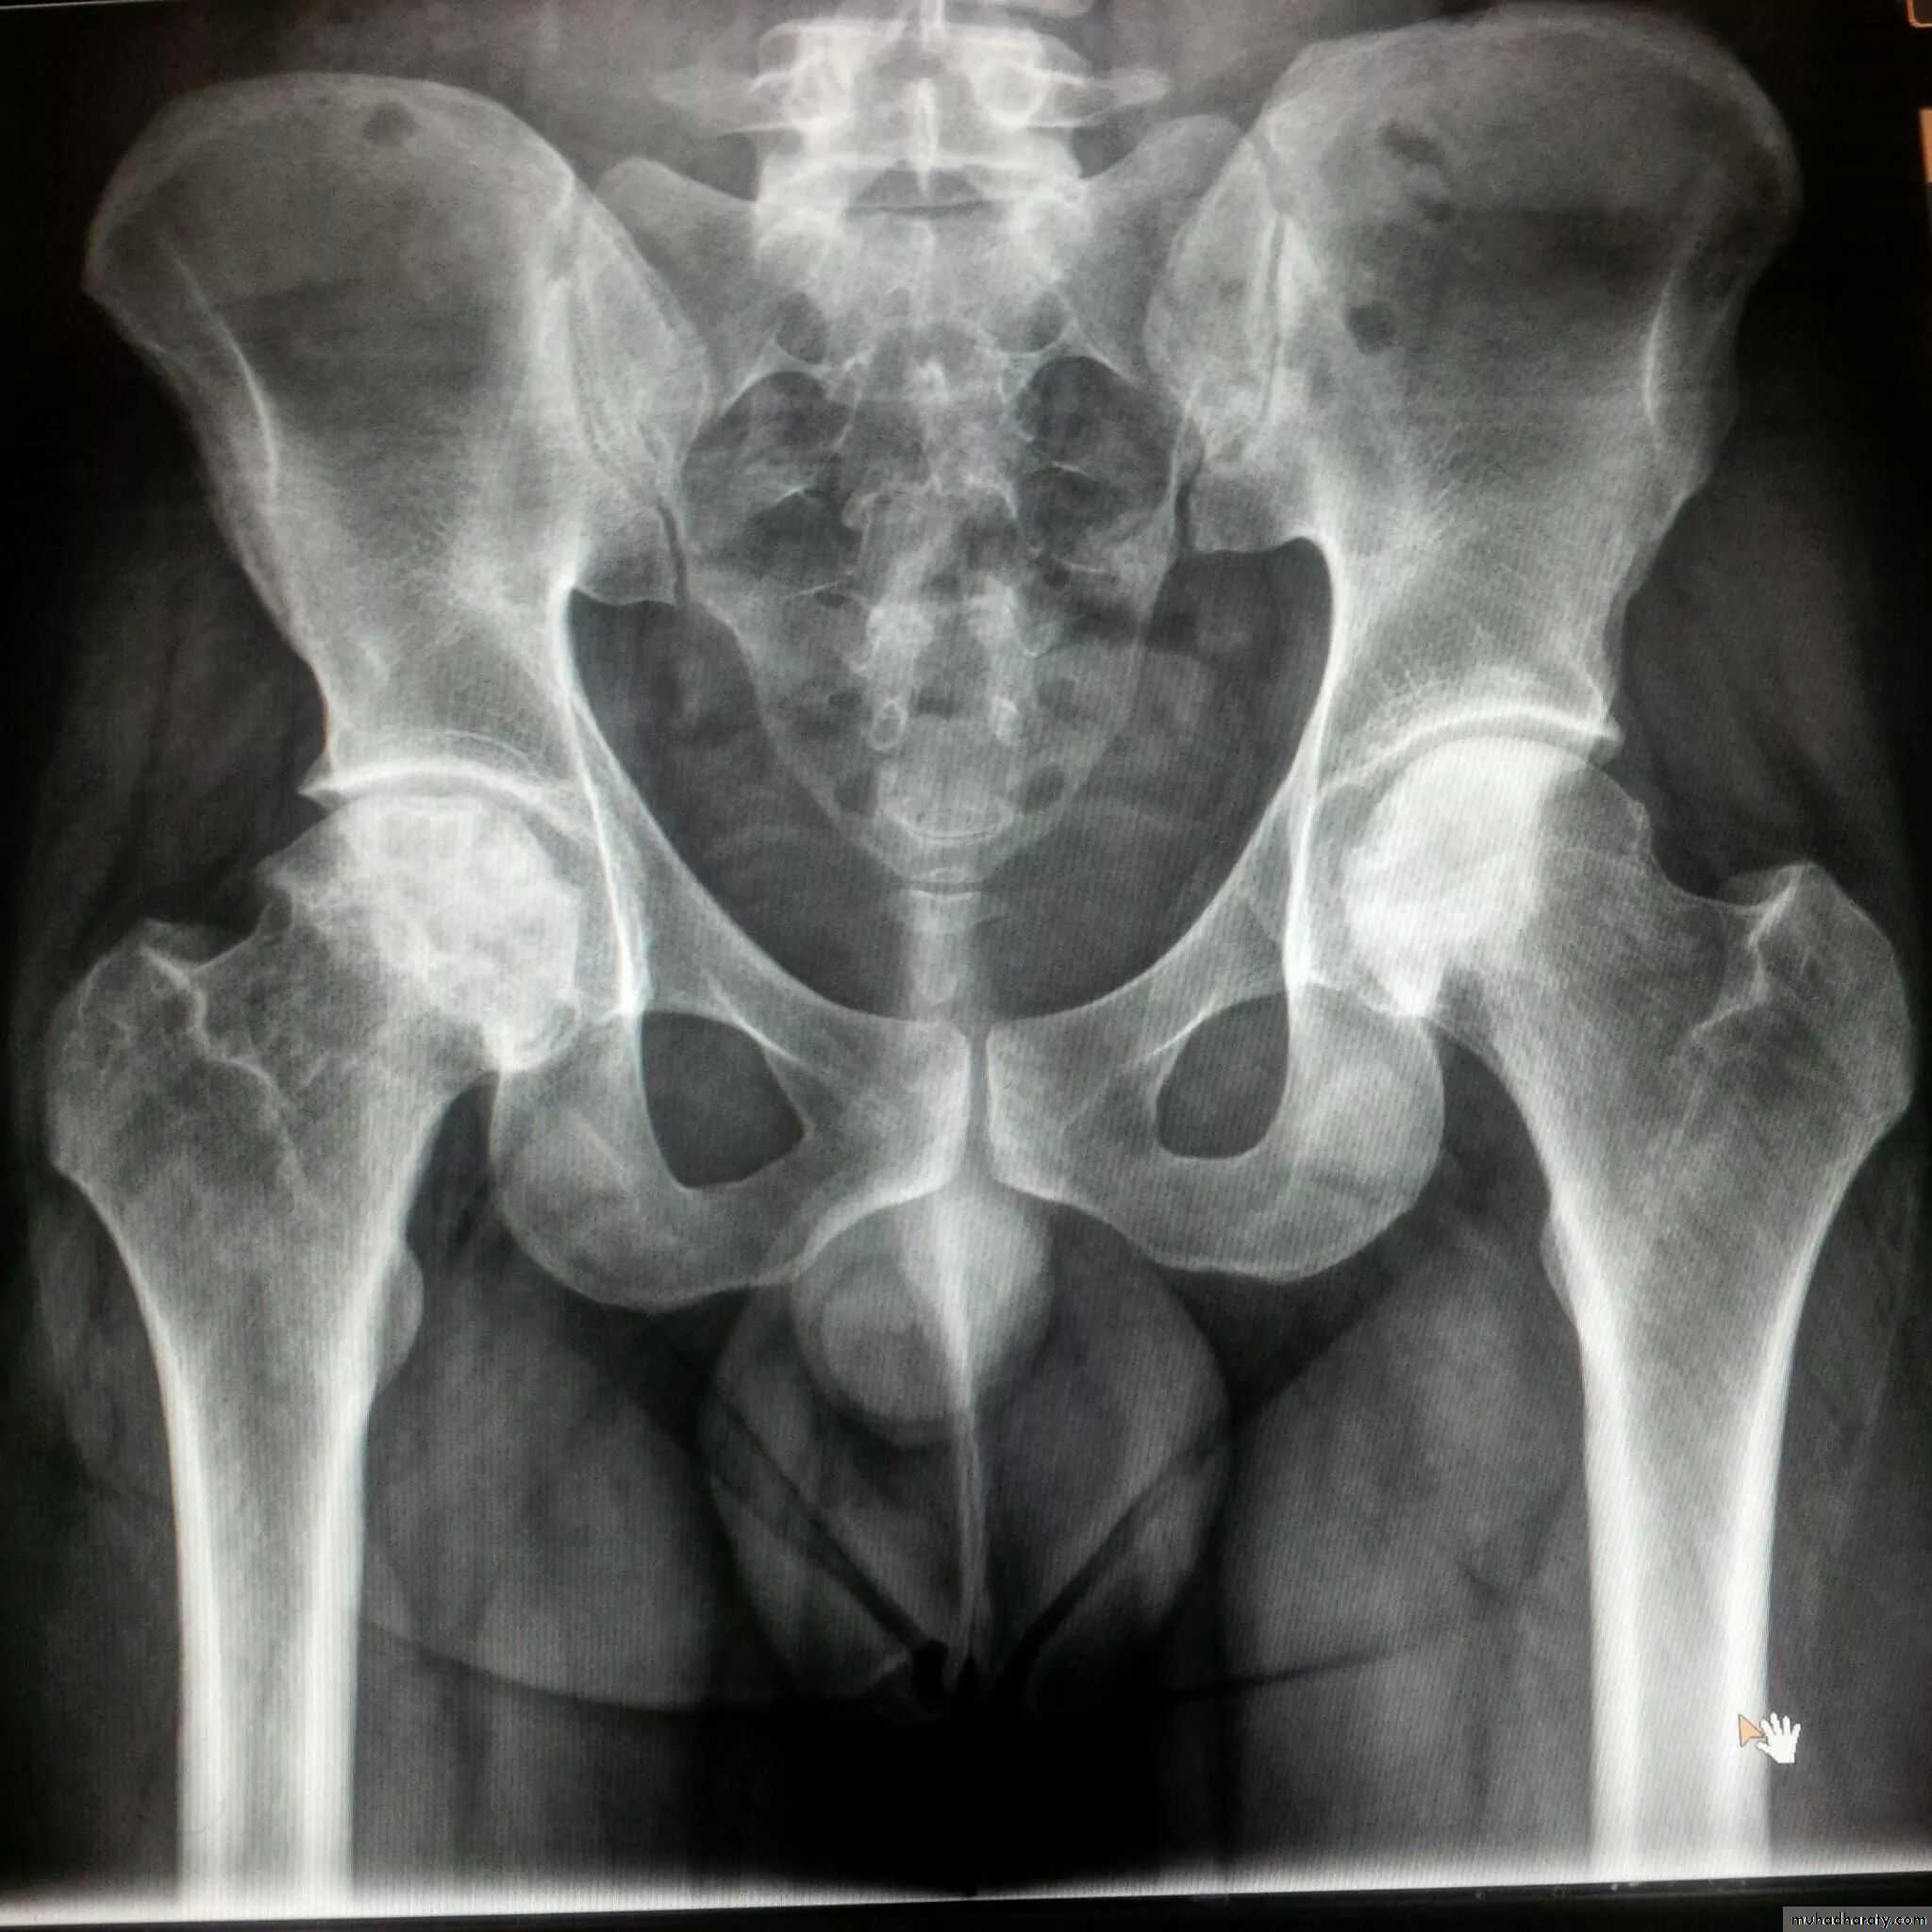

There are three types of arthritis which ca be distinguished radiologically :

1. Degenerative arthritis:Osteophytes

Subcondral sclerosis

Uneven loss of articular space

The joints commonly involved are DIP, 1st carpal-metacarpal, knee, hip and spine

OA – Radiographic findings1. Joint space narrowing

2. Osteophyte formation (white arrow)3. Subchondral sclerosis (black arrows)